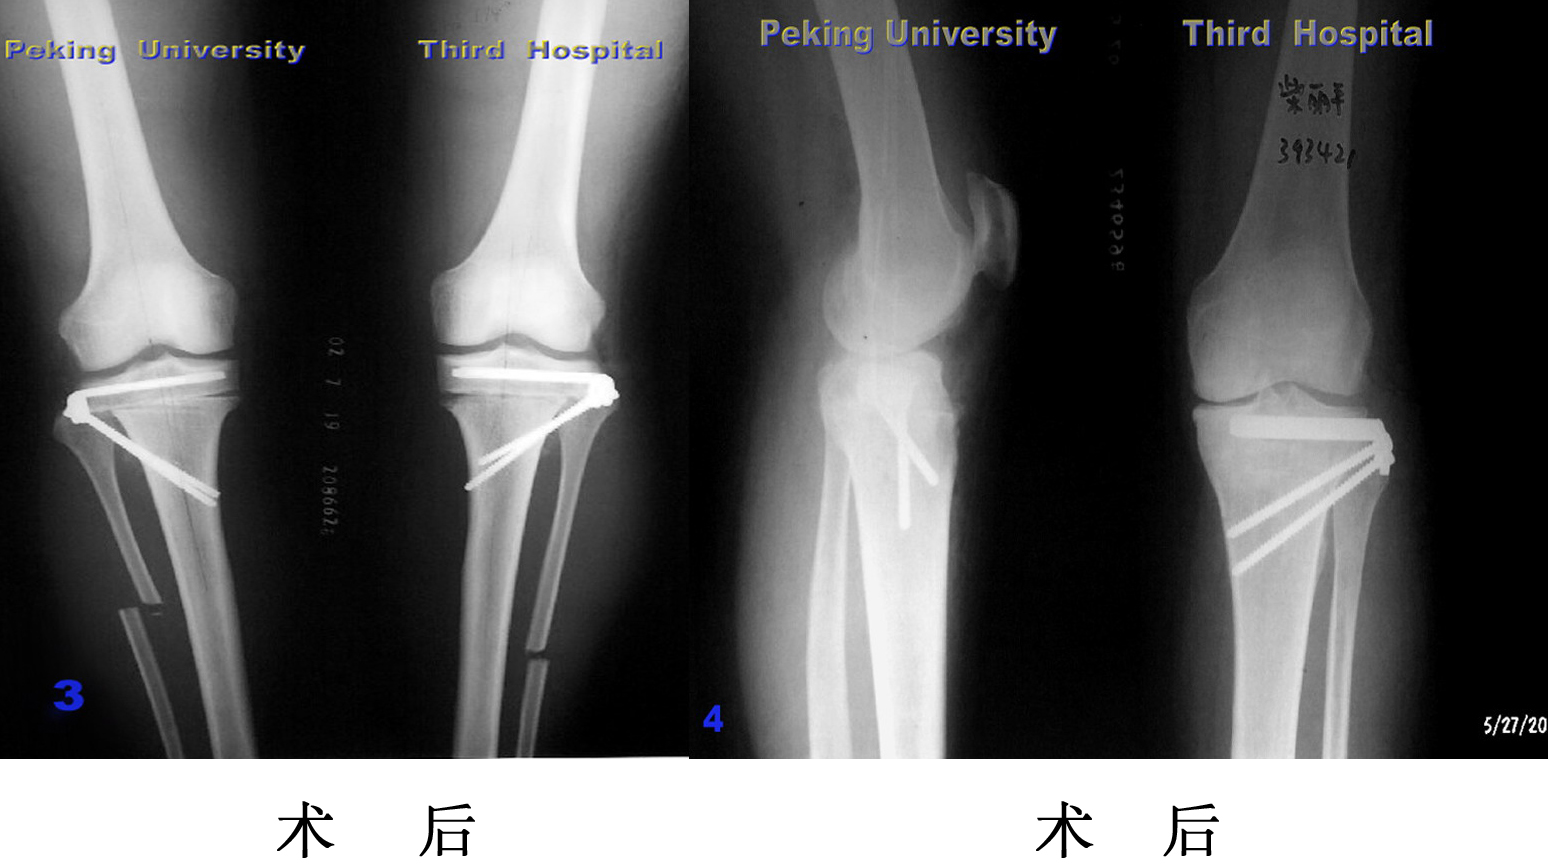

胫骨截骨

胫骨植骨

严重膝内翻,胫骨平台内侧植骨,软组织松解,术后内翻纠正

内 翻